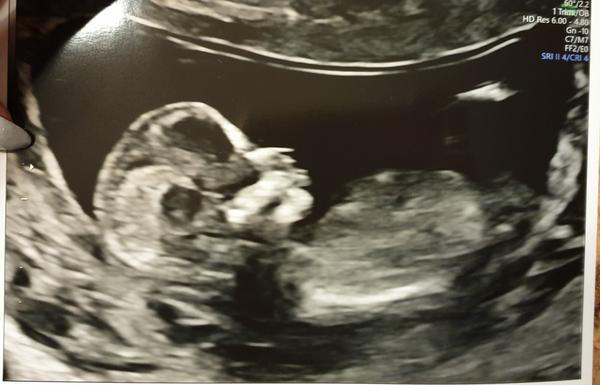

Co vidíte na ultrazvukové fotce ve 22. týdnu?

Nevím, jestli tam mám vidět piňďulu nebo čárku 🤷♀️😅

Co vidíte na fotce vy? 😊

Myslím, že holka, nevidím tam varlata a to uprostřed mi přijde jako pupeční šňůra.

Asi holčička. Nic navíc tam nevidím. A jinak je ten dr. pěknyýblbec, teda.